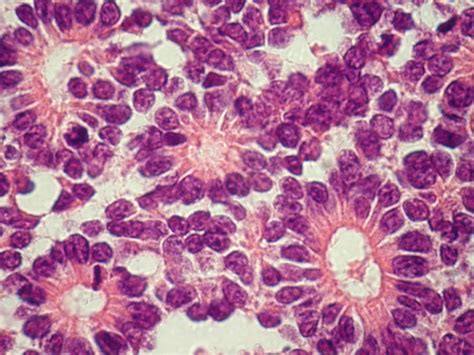

At their core, Homer Wright rosettes are histologic features characterized by clusters of tumor cells arranged in a circular or flower-like pattern around a central core. This central area is not composed of a vessel or a lumen; rather, it consists of a dense tangle of neuropil—the meshwork of axons, dendrites, and glial cell processes. Unlike other types of rosettes where the cells are arranged around a central blood vessel, the lack of a vascular lumen in these structures is a definitive feature for identification.

These structures were named after James Homer Wright, an American pathologist who first described them while studying neuroblastomas. They serve as a morphological indicator that the tumor cells have retained some degree of neuroblastic differentiation, even within a highly malignant environment. Their presence provides a vital clue to the origin of the tumor, steering the diagnosis toward the neuroectodermal lineage.

The primary clinical value of identifying Homer Wright rosettes lies in their diagnostic utility for specific types of tumors. They are most notably associated with neuroblastoma, medulloblastoma, and pineoblastoma. Because these tumors are often aggressive and require prompt, specific treatment protocols, recognizing these patterns early is paramount.

💡 Note: When examining a slide, look for the 'halo' effect created by the peripheral tumor nuclei, which helps highlight the central neuropil core more clearly.

The formation of Homer Wright rosettes reflects the biological drive of primitive neuroectodermal cells to differentiate. These cells are attempting to organize themselves into neuronal-like structures. The central neuropil is essentially a localized collection of neurites—the projections of the tumor cells themselves. This indicates that the tumor is not merely a mass of disorganized, rapidly dividing cells, but one that possesses an underlying (albeit chaotic) developmental program reminiscent of normal neural development.